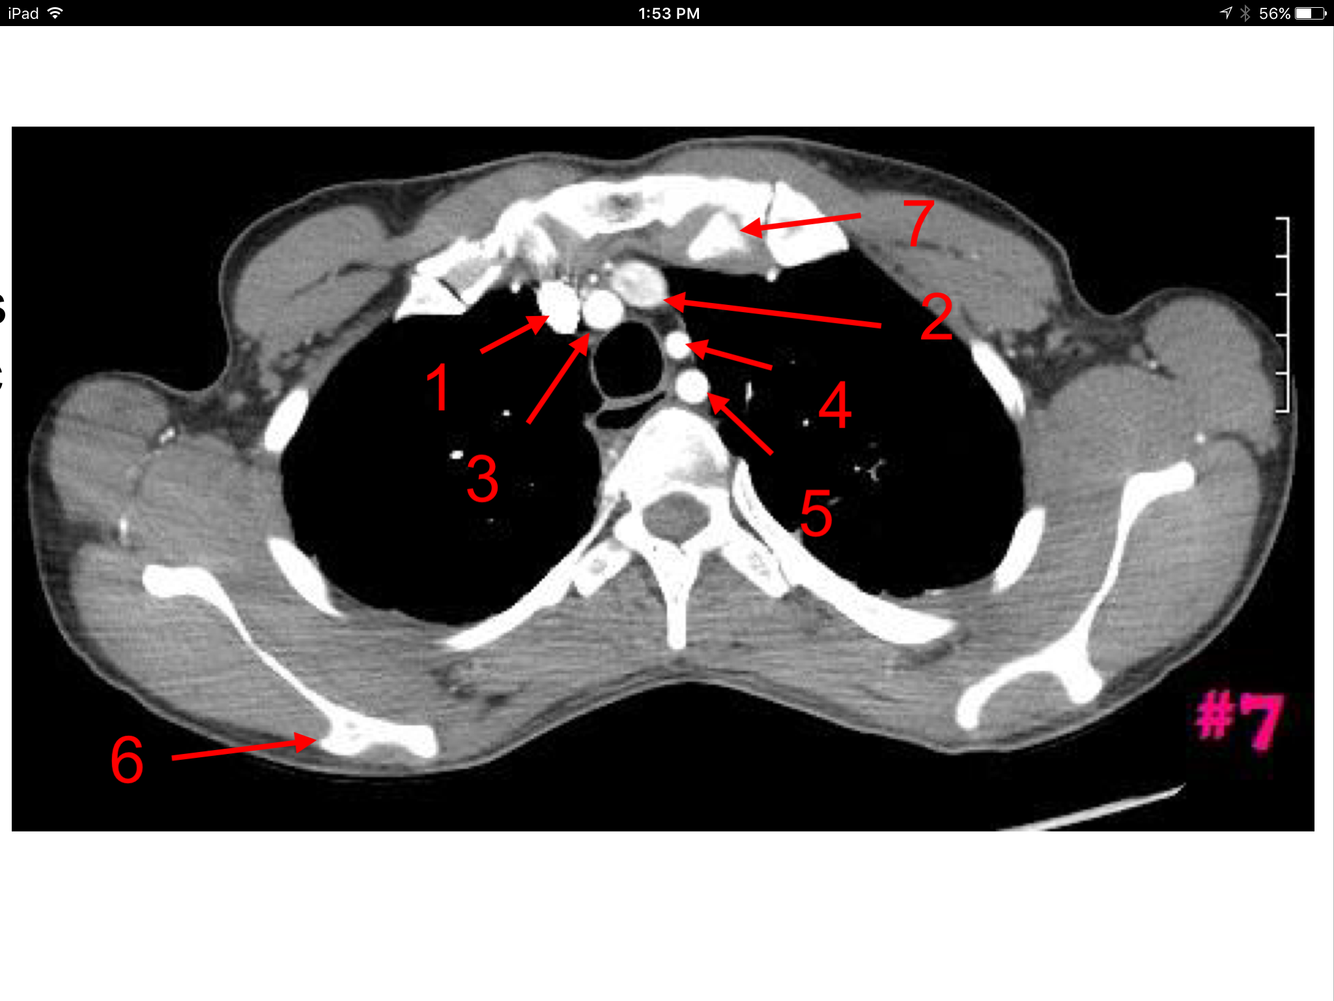

Rt brachiocephalic vein

Lt brachiocephalic vein

Brachiocephalic artery

Lt common carotid artery

Rt pectoralis minor muscle

Rt pectoralis major muscle

Lt costotransverse articulation

Rt costovertebral articulation